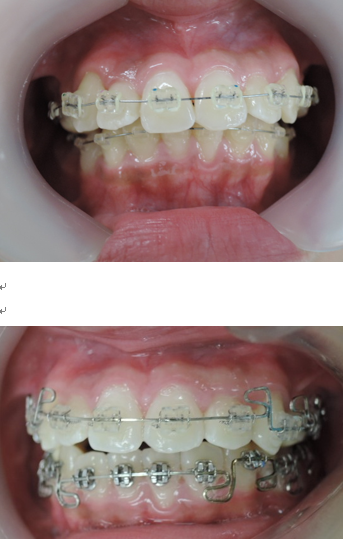

よく診る、難しい症例(奥歯の隙間)